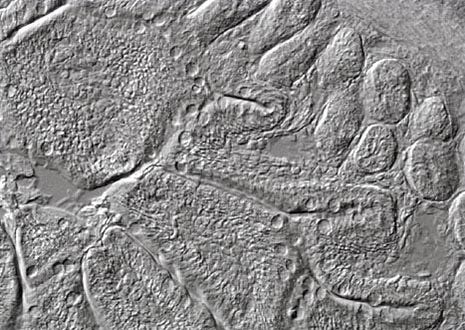

Intestine Thin Section

The digestive systems of most higher-level animals have the same basic components: mouth, pharynx, esophagus, stomach, small intestine, and large intestine. The relative importance and specific characteristics of each component, however, are highly dependent upon the typical diet of the species.